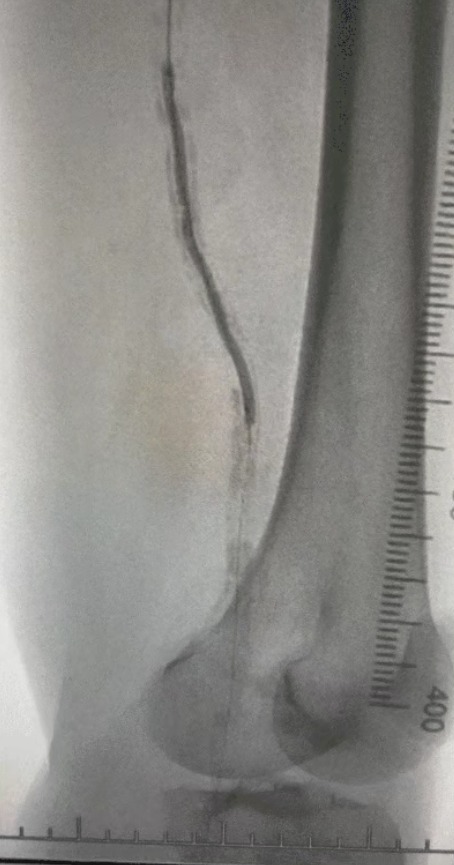

· Körperliche Untersuchung: Schwache Femur impulse; fehlende Popliteal-und Dorsalis-Pedis-Impulse; Geschwür am linken ersten Zeh; Nekrose am rechten ersten und zweiten Zehen

· Präoperative Bildgebung: Schwere, diffuse verkalkte Stenose in bilateralen Arterien der unteren Extremitäten

Angesichts des komplexen Gefäß zustands haben wir das ThorCrack Periphere IVL-Ballon dilatation katheters ystem ausgewählt. Aufgrund der begrenzten Toleranz des Patienten wurden inszenierte intervention elle Eingriffe an beiden unteren Gliedmaßen durchgeführt.

Nach dem Eingriff verbesserte sich die arterielle Stenose signifikant, der Blutfluss stieg und die Haut temperatur stieg. Es traten keine postoperativen Komplikationen auf. Sowohl der Patient als auch das Operations team waren mit den Ergebnissen sehr zufrieden.